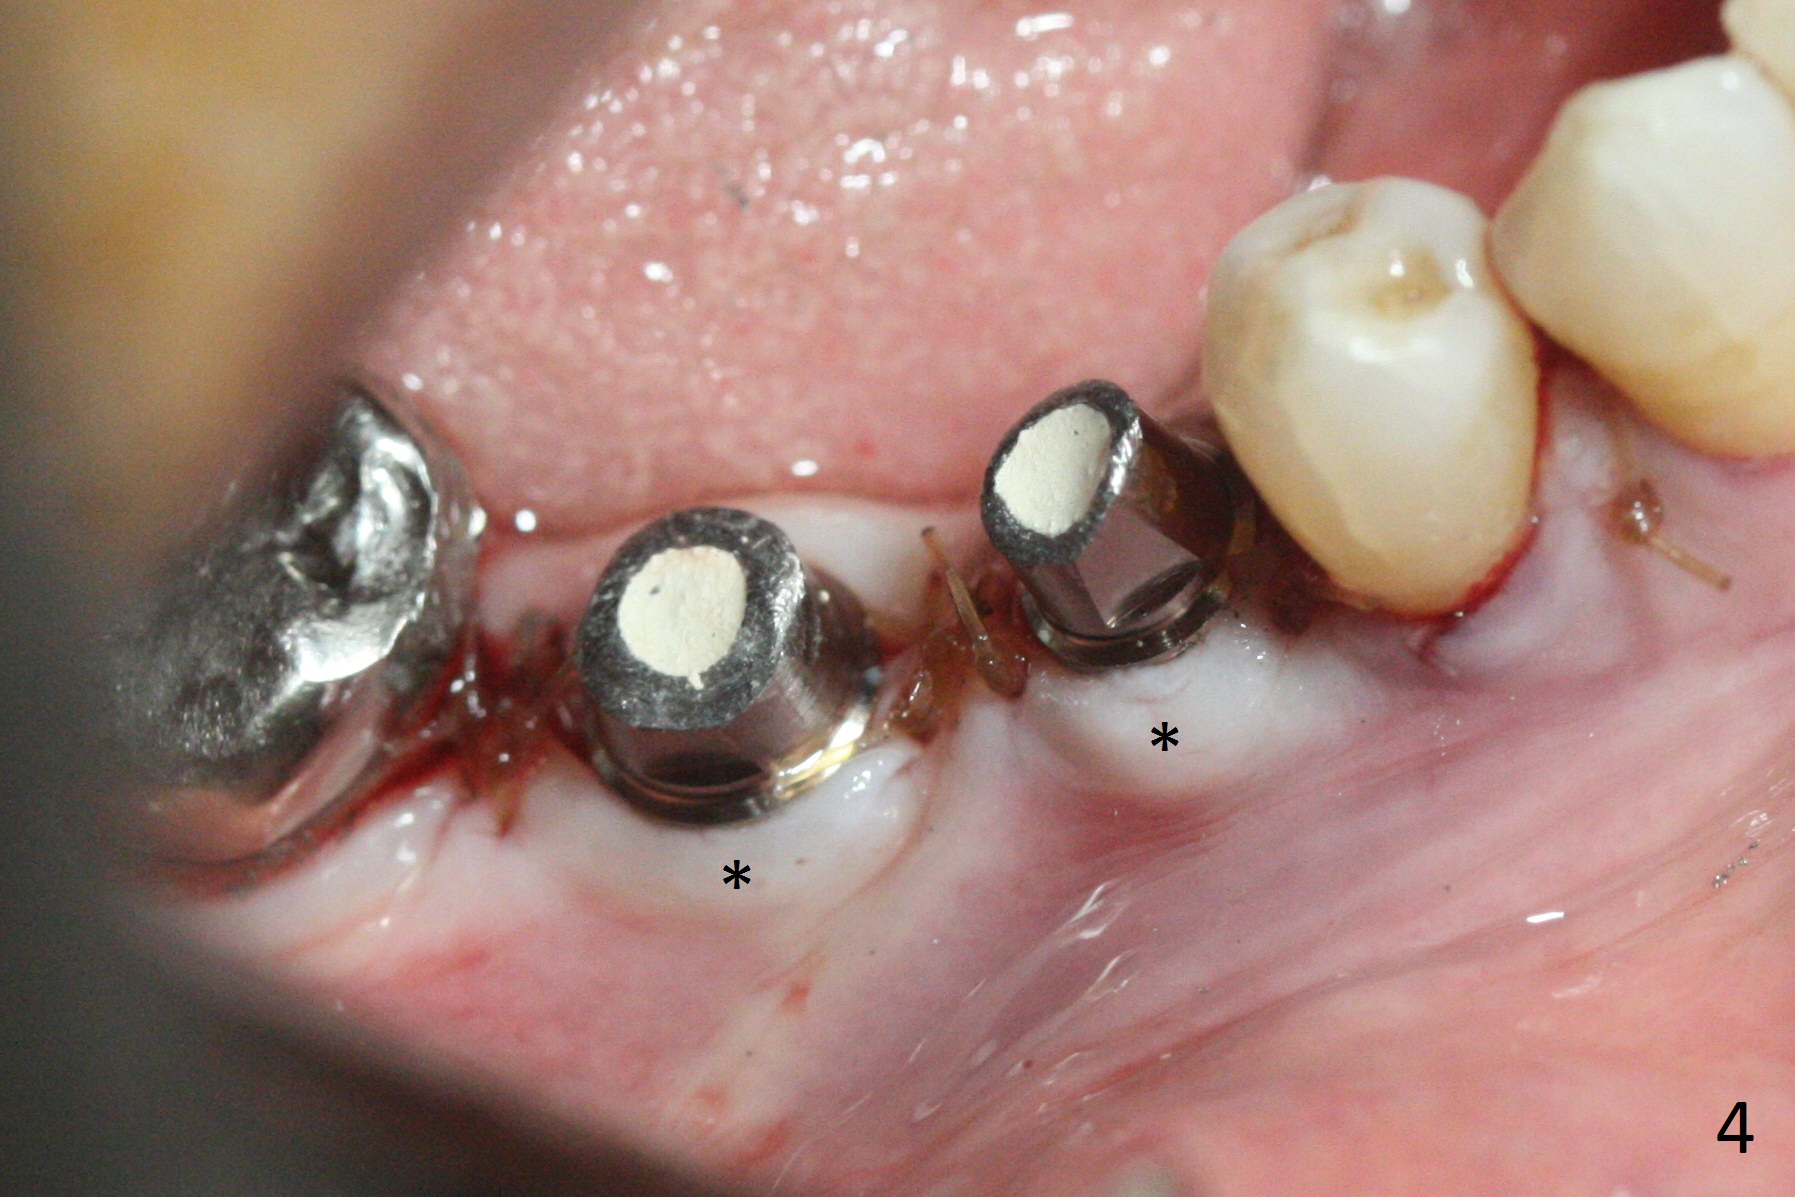

After incision, the ridge at #29 and 30 is found ~ 5 mm wide buccolingually. To place a 4x11 mm IBS implant at #30, the ridge is expanded using BEB technique (bone expansion and bending, Fig.1). It appears that the initial osteotomy at #29 is mesial (Fig.1 yellow dashed line: the distal surface of the root of the tooth #28). After moving the osteotomy distal, the final implant position at #29 (4x11 mm) is within normal limit (Fig.2). The bone at #29 seems to be not so dense that bending (using 1.6 mm drill) is not necessary (using Magic Split and Magic Expanders 3 and 3.8 mm). Later the implant at #30 (4x11 mm) is placed deeper (Fig.3). After placing bone graft around the implants/abutments and suturing, the ridge looks wider with apparent formation of the gingival bands around the abutments (Fig.4 *). Three months and a half postop, bone loss is minimal (Fig.5) and gingival bands forms around the abutments (Fig.6). Fig.7 is taken 1 month post cementation (panoramic X-ray). The patient chews normally 1 year (Fig.8) and nearly 2 years (Fig.9,10) post cementation. The crown at #31 needs recementation 2 years 7 months post #30 cementation; the incomplete seating of the abutment was noted for the first time (Fig.11). Five months later the patient is going to be retired and wants to travel abroad. After approval, the access hole was reopened; articulating paper shows under occlusion of the crown (Fig.12). Since the gap between the abutment and the implant is large, the abutment/crown complex seems to be necessary to be turned (Fig.13 curved arrow). The proximal surfaces of the crown need to be trimmed (straight lines). After turning, the crown sits down with screw tightening; the patient feels pain from the gingival cuff (Fig.14). After turning, the abutment appears to be completely seated (Fig.15). In fact the mesial and distal surfaces of the crown should have clearance from the neighboring teeth (Fig.14) so that pick-up impression is able to hold the crown/abutment complex securely (Fig.16: *). The crown is separated from the abutment after crown repair. They are seated together (loose connection) using the crown as a guide to seat the abutment. BW is taken without the crown. It appears that the abutment remains seated completely (Fig.17). The apical space is equal between #29 and 30 (Fig.17, as compared to Fig.5).